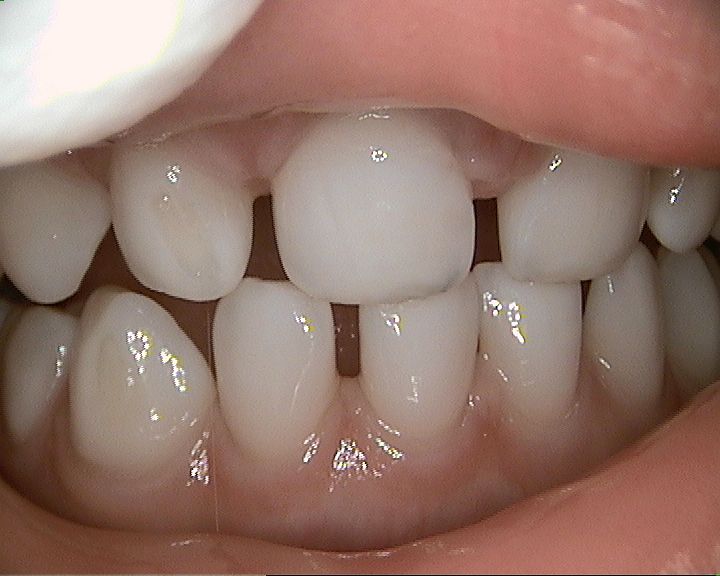

![]() Nichts mehr zu sehen von der Karies - eine gelungene Füllung trotz kleinem Mund und kleinem Kind